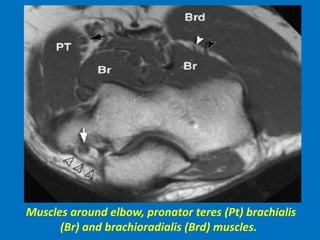

Muscles around elbow, pronator teres (Pt) brachialis

(Br) and brachioradialis (Brd) muscles.

Muscles around elbow,pronator teres (Pt) brachialis (Br) and brachioradialis (Brd) muscles.